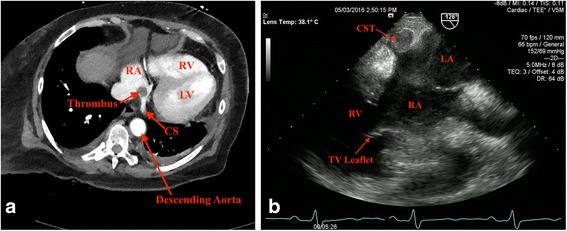

Computed tomography (CT) of her abdomen and pelvis with intravenous contrast was negative for acute intra-abdominal pathology including thrombosis of the hepatic veins, but incidentally identified an oval-shaped filling defect at the junction of the right atrium and CS suspicious for thrombus or mass (Fig. 1a). Transesophageal echocardiogram (TEE), a better imaging modality for tissue characterization and assessment of the right atrium and CS, demonstrated a 1.5 × 1.5 cm echogenic globular mass at the ostium of the CS consistent with thrombus (Fig. 1b). The left ventricle was normal in size, but systolic function was mildly depressed.

Fig. 1.

a Chest computed tomography with contrast at the level of coronary sinus showing an oval-shaped filling defect at the junction of the right atrium and coronary sinus suggestive of coronary sinus thrombus. b Transesophageal echocardiogram at the gastroesophageal junction positioned at 126° demonstrating a 1.5 × 1.5 cm echogenic globular mass at the ostium of the coronary sinus. CS coronary sinus, CST coronary sinus thrombus, LA left atrium, LV left ventricle, RA right atrium, RV right ventricle, TV tricuspid valve